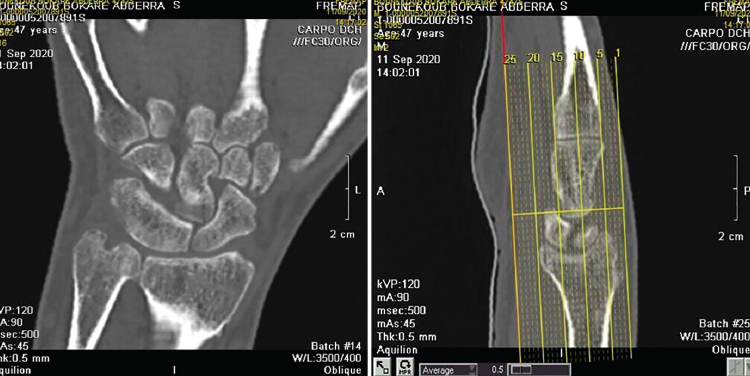

Figura 1. Radiografía de muñeca. Proyección anteroposterior.

Se solicitan estudios de imagen. En primer lugar, rayos X de muñeca en proyección anteroposterior (AP) (Figura 1), en los que se evidencia un aumento del espacio cubital y presencia de la fusión lunopiramidal. Se coloca una inmovilización con muñequera elástica. Se solicita (Figura 2) tomografía axial computarizada (TAC) para la confirmación del diagnóstico y resonancia magnética (RM) (Figura 3) de mano para valorar las estructuras blandas. Los hallazgos de la TAC reportan la coalición lunopiramidal de tipo Minnaar III y la RM realizada para valorar lesiones asociadas de partes blandas reporta sinovitis. El resto de los elementos no muestran alteraciones.